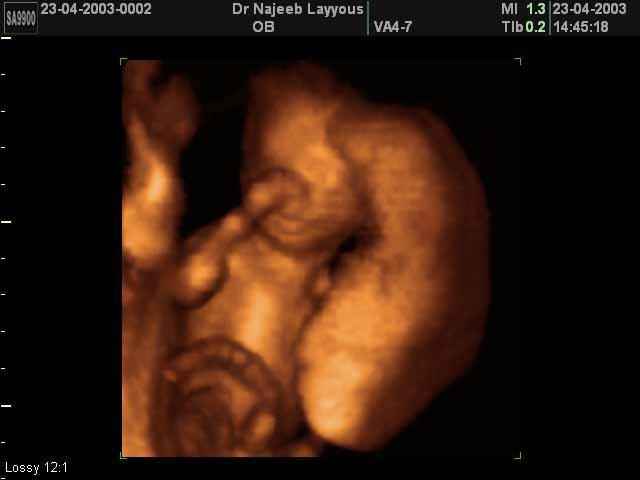

3D second trimestre échographie Photos de numérisation - deuxième partie de la grossesse